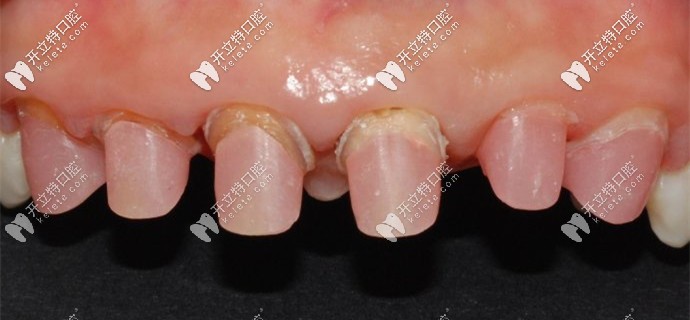

被磨掉1/2的基牙

牙醫(yī)說我的牙齒情況不容樂觀,之前醫(yī)生操作不當(dāng)?shù)脑颍瑢?dǎo)致牙槽骨萎縮、基牙腐爛,只能建議拔掉做種植牙。

我的基牙已經(jīng)腐爛了只能做種植牙